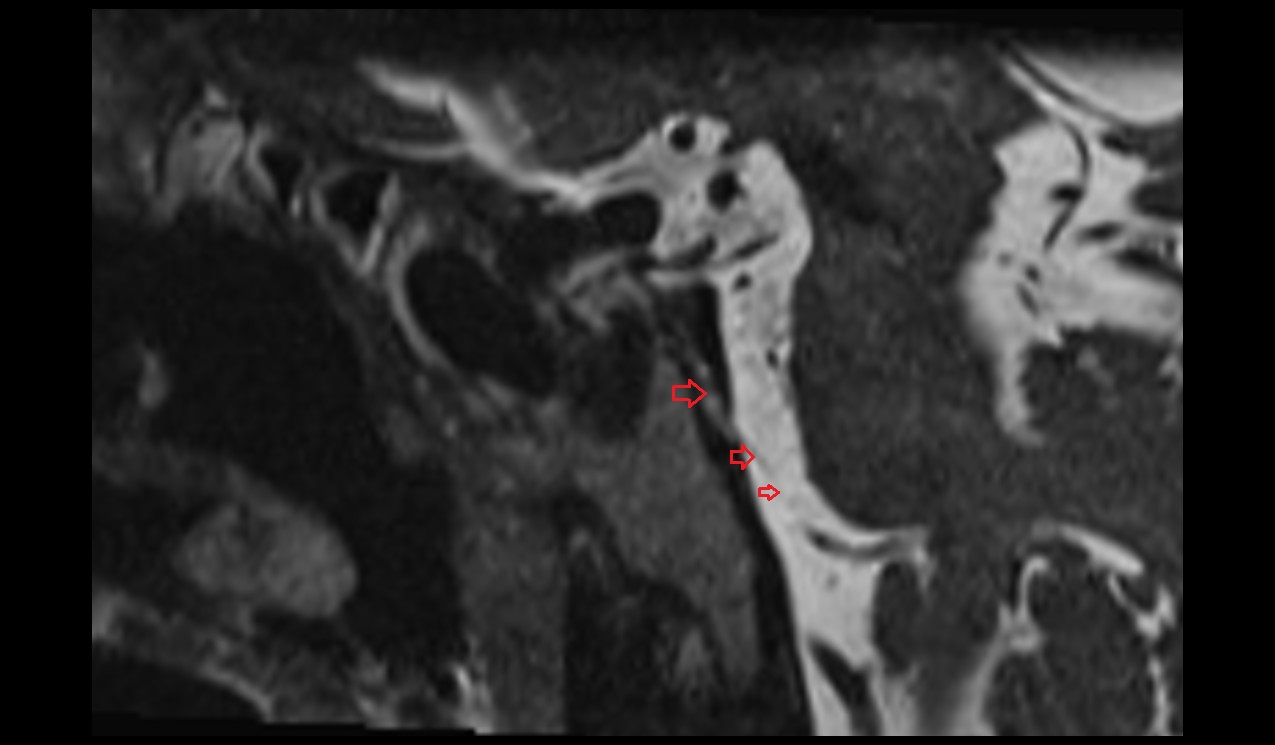

- Temporomandibular joint

- Articular disc of temporomandibular joint

- Articular eminence

- Mandibular condyle

- Mandibular fossa